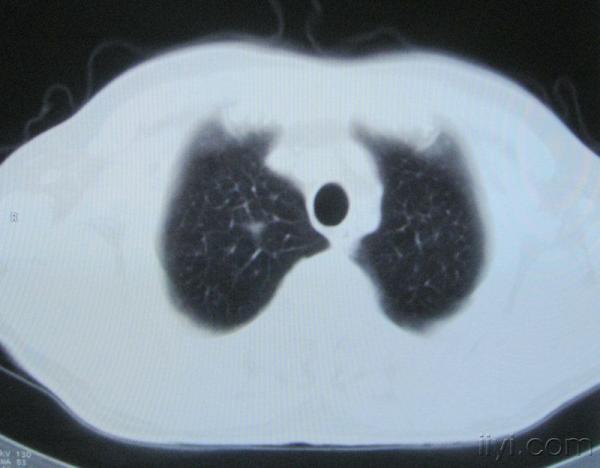

男。60岁,胸片示支气管炎治疗后复查CT。